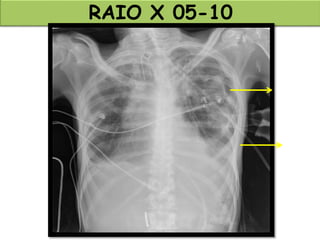

RAIO X 05-10

RAIO X 08-10